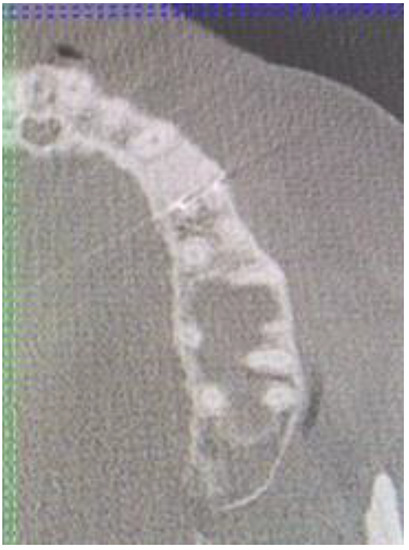

A 35-year-old female patient presented with a small, well-defined lesion on the attached gingival area, approximately 5/6 mm in diameter between roots of teeth 23–24, reported to the Privat Dental Clinic. The patient’s main concern was focused on gingival asymmetry and a tumor-like mass, painless and sometimes tender on tooth brushing. Clinical anamnesis revealed the occurrence of this asymptomatic mass for over 6 months. Because of swelling and atypical cortical expansion, the patient was referred for consultation and treatment. The patient was generally healthy without any chronic illness or important medical and dental past. A routine panoramic radiograph revealed a well-defined, radiolucent, left maxillary lesion located between the roots of the canine and first maxillary premolar (Figure 1 and Figure 2).

Figure 3. CBCT sagittal view of LPC.